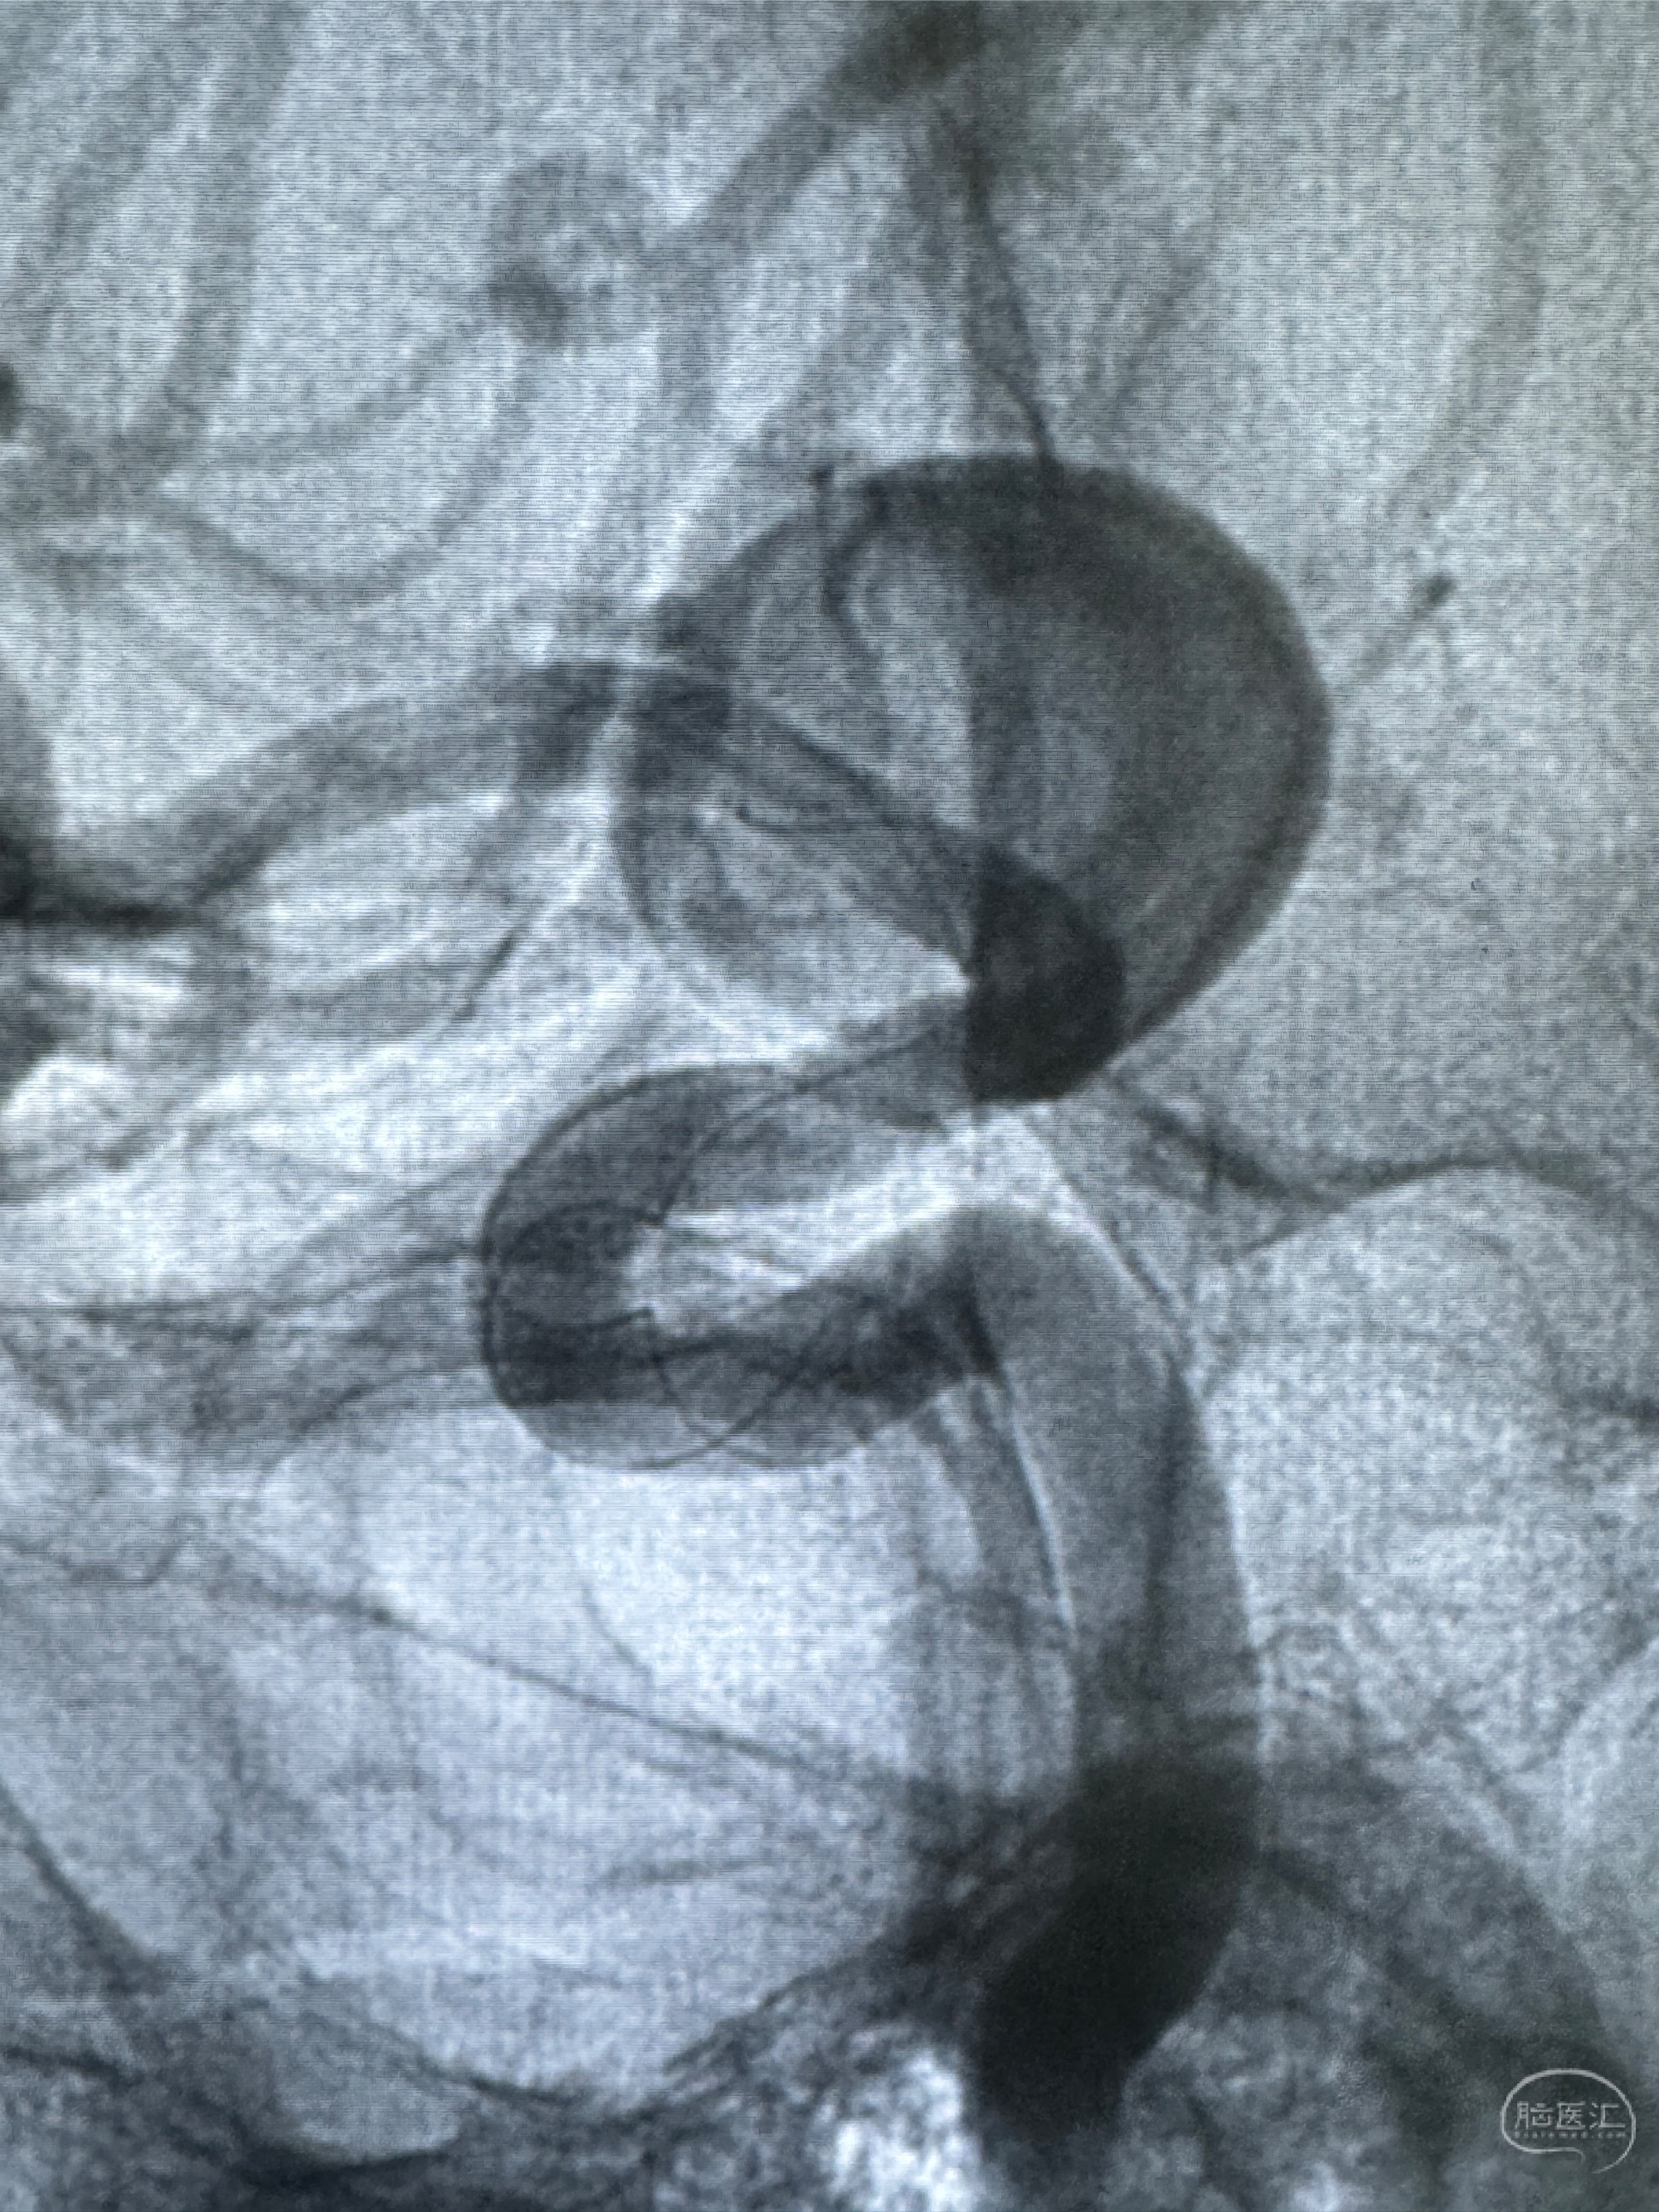

现病史:患者诉2年来反复发作性头痛,顶枕部为主,因自己考虑高血压可能,未予系统检查;患者约20日前无明显诱因下突发剧烈头晕,有天旋地转感,不能睁眼,伴视物模糊;外院查头颅MRI+MRA提示:左侧颈内动脉C6段动脉瘤;遂至复旦大学附属华山医院就诊,于2023-12-08行全脑血管造影提示:右侧颈内动脉C6段动脉瘤,瘤颈6.68mm,动脉瘤大小13.28*12.34mm,建议行密网支架辅助栓塞术治疗,因缺乏相关材料遂出院。现患者仍有顶枕部头痛不适,为求进一步诊疗脑血管病变至我科就诊,收治入院。

2023-12-08 复旦大学附属华山医院 全脑血管造影:右侧颈内动脉C6段动脉瘤,瘤颈6.68mm,动脉瘤大小13.28*12.34mm

2023-12-08外院DSA:右侧颈眼动脉瘤,约13*12mm大小,压颈试验显示左右向及后向前代偿可

测量动脉瘤的大小:16*13.8*7.6mm大小,较原先变大,考虑双抗后瘤内血栓溶解可能

观察动脉瘤腔内的血流动力学情况